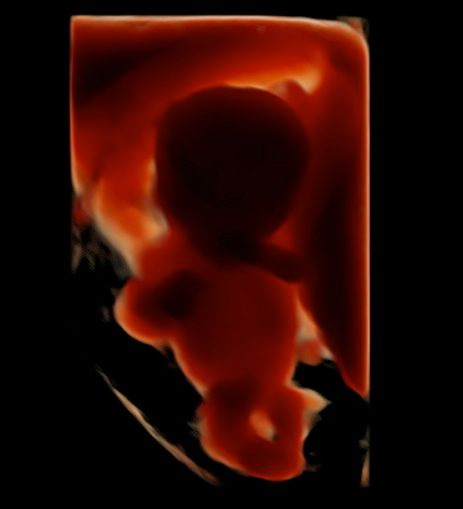

Foto e video